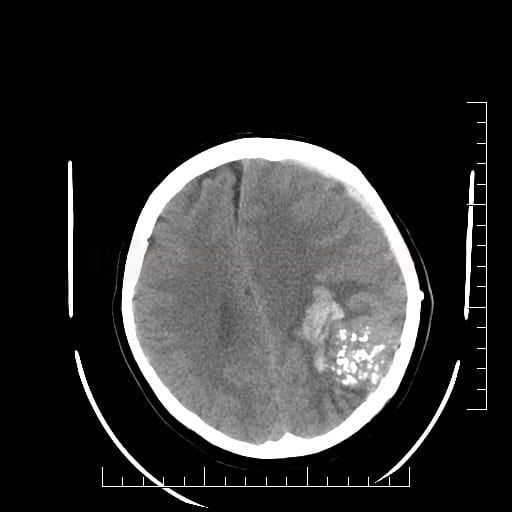

Компьютерная венография выявляет следующие признаки венозной мальформации мозга:

В нативном режиме выявляются извилистые или линейные образования с незначительной гиперденсностью, соответствующие скоплениям венозных сосудов без признаков масс-эффекта.

В венозной фазе определяется равномерное интенсивное контрастирование венозных каналов, сходящихся к одному или нескольким расширенным дренажным венам.

Определяется характерная конфигурация сосудистого рисунка в виде «короны» или «головки медузы» с чёткими границами.

Не выявляется перифокальный отёк или деструктивные изменения мозгового вещества в области венозного скопления.

Срединные структуры остаются интактными, смещения не наблюдается.